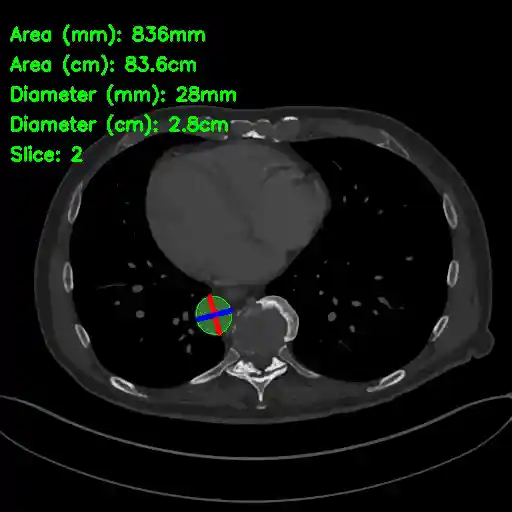

AAA Segmentation and Maximum Diameter Measurement

Example Output Image (slice with largest diameter)